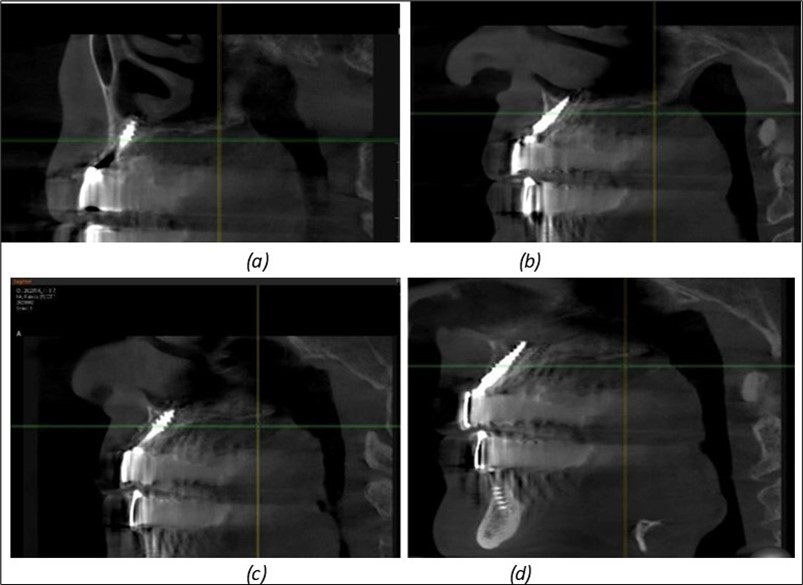

Figure 11.Implants in the anterior area anchored in the nasal cortex (BCS and TPG): (a), (c) – BCS implants fixed in the nasal cortex; (b), (d) – TPG implants fixed in the second nasal cortex with compression in the trabecular area.